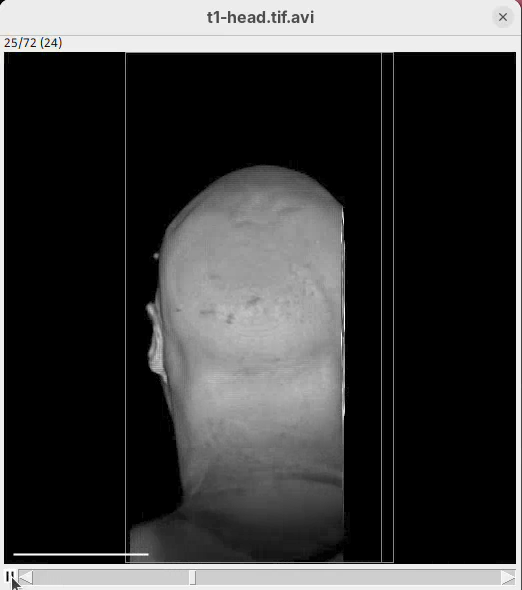

The BigDataViewer interface will open showing an optical section of the head sample.

Some of the movements to try:

Left-click and drag: turn the sample around the mouse pointer at any arbitrary angle.Right-click and drag: move the sample in the XY plane (of the view).Scroll: move through the Z plane (of the view). UseShift+Scrollto move fast.Ctrl+Shift+Scroll: zoom in or out.

But, most importantly, are the commands to put your sample back to its original orientation or along any of the original dimension axes:

Shift+Z: orient the sample on the XY plane.Shift+X: orient the sample on the ZY plane.Shift+Y: orient the sample on the ZX plane.

Finally, a visual tip. The default interpolation between image slices is nearest-neighbors. Press I to activate the tri-linear interpolation to obtain a much smoother (and improved) data visualization.